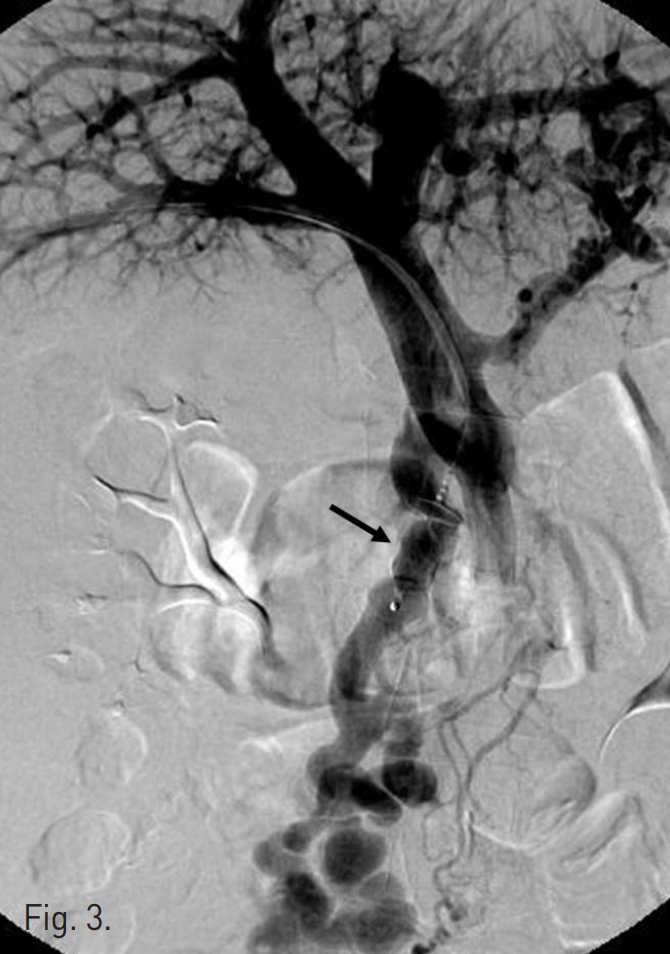

12mm AMPLATZER® Vascular Plug(AVP; AGA Medical, Golden Valley, MN)를 이용하여 주문맥의 원위부에서 기시하는 비후된 afferent vein에 대한 색전술을 시행함(Fig.3). 이후 시행한 direct portal venogram에서 상장간막 정맥으로부터 기시하여 varix nidus를 supply하는 3개의 측부혈관(collateral vessels)이 관찰되고 이로부터 varix의 nidus가 retrograde filling되는 소견이 지속적으로 관찰됨(Fig.4). 이에 대하여 2.4F microcatheter(Progreat®; Terumo, Tokyo, Japan)를 이용하여 각각의 측부혈관을 선택한 후 다수의 microcoils(Tornado®; Cook, Bloonminton, USA)을 이용하여 색전술을 시행함.

Fig. 3

The main trunk of jejunal varix is embolized with 12mm in diameter vascular plug (arrow).